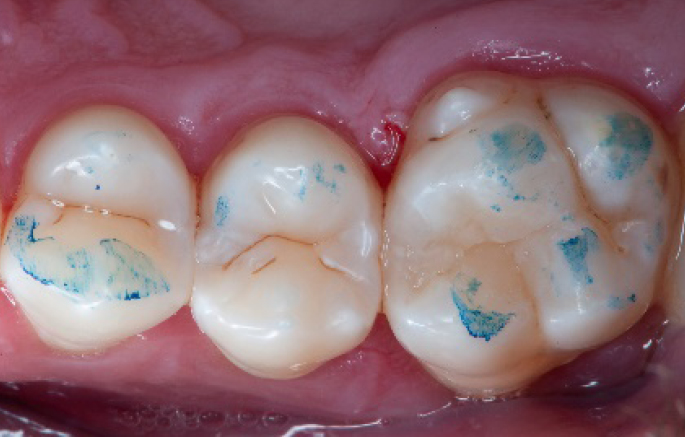

Step 2:

Initial cavity preparation, protecting the adjacent tooth with a Palodent1 WedgeGuard.